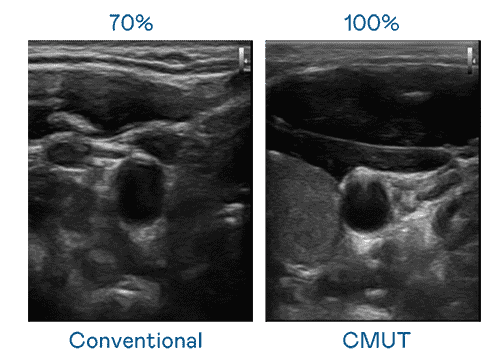

CMUT 技术是一种用电容式微机电元件来产生超音波讯号的技术。。与传统 PZT 压电式技术相比,,,CMUT 频宽增加 30%,,更宽频的超音波讯号让影像解析度大幅提升,,是实现高影像品质医疗超音波扫描、、、促进精准医疗发展的关键技术。。

大频宽带来超清晰影像

超音波影像的解析度高低,,首先取决于探头能发出的讯号频宽。。彩霸王 CMUT 可提供高清晰的超音波讯号,,,提供高频宽、、、、高灵敏度、、、影像纹理细节更高的超音波影像,,,协助医护人员缩短影像判读时间及利用精准的医疗影像进行诊断。。。